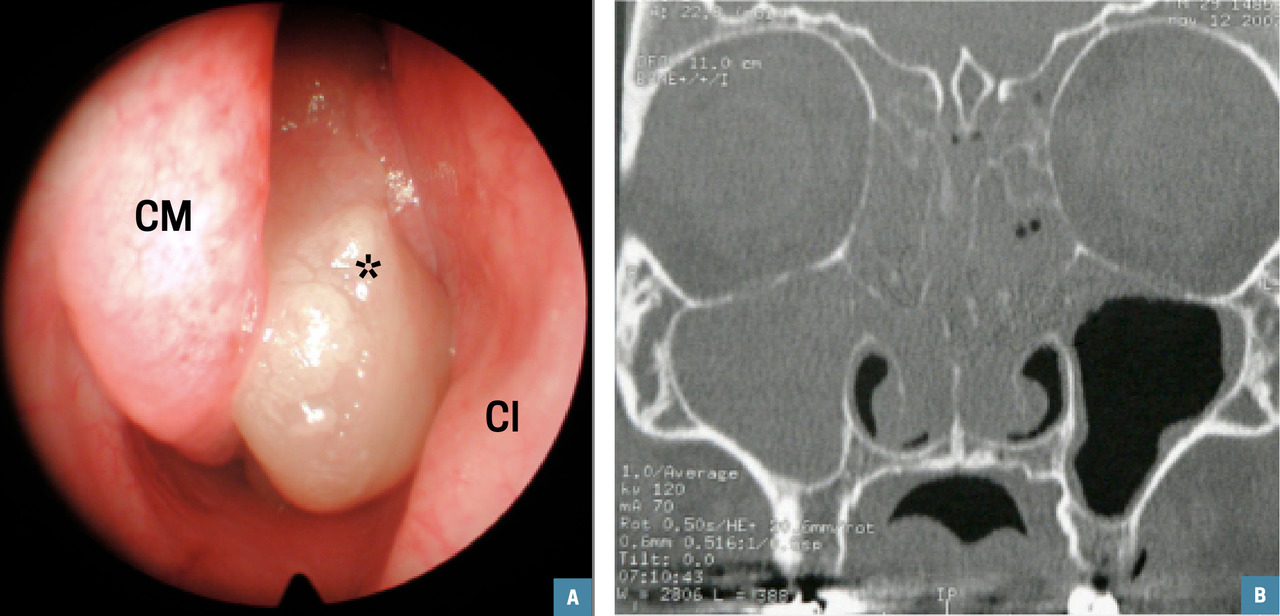

Polypose naso-sinusienne : vue endoscopique d’un polype au niveau du méat moyen gauche (A, étoile) ; aspect d’opacités naso-sinusienne diffuses sans lyse osseuse sur la tomodensitométrie (B).CM : cornet moyen ; CI : cornet inférieur